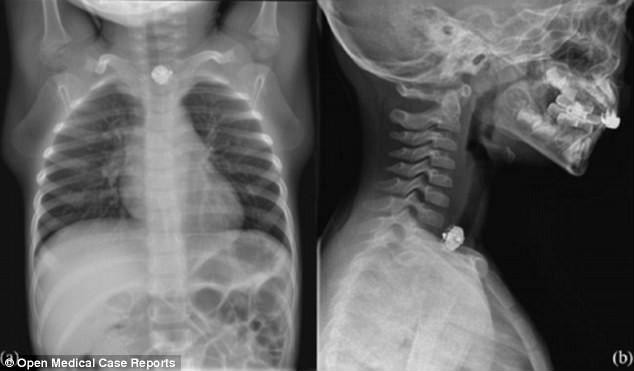

Ảnh chụp X-quang cho thấy dị vật bị mắc kẹt bên trong thực quản của cậu bé

Cậu bé được giấu tên đã được chuyển đến trung tâm y tế Đại học Texas Southwestern khoảng 2 tiếng sau khi nuốt bảng mạch điện tử kèm pin. Bộ phận này là từ một chiếc spinner có đèn. Hình ảnh từ phim chụp X-quang cho thấy bộ phận nhỏ xíu của món đồ chơi đã bị mắc kẹt bên trong thực quản của bệnh nhân. Sau 4 tiếng nằm trong cổ họng, bảng mạch này đã được gắp ra thành công.